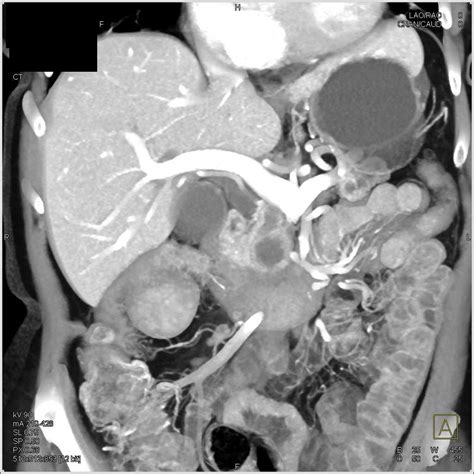

To understand dilation, one must first understand the anatomy. The main pancreatic duct, or the Duct of Wirsung, typically runs the length of the pancreas. In a healthy individual, this duct has a specific, narrow diameter. When a radiologist performs an ultrasound, CT scan, or MRI and notes an enlarged pancreatic duct, they are observing that the diameter of this duct exceeds the normal, expected measurement. This dilation is rarely a condition in itself; rather, it is usually a symptom or a sign of an underlying issue causing back-pressure or blockage within the ductal system.

• Pancreatic Cysts: Certain types of cysts, such as Intraductal Papillary Mucinous Neoplasms (IPMNs), can grow within the duct and cause it to expand.

CT Scan with Contrast Provides detailed cross-sectional images to look for masses, inflammation, or large stones.